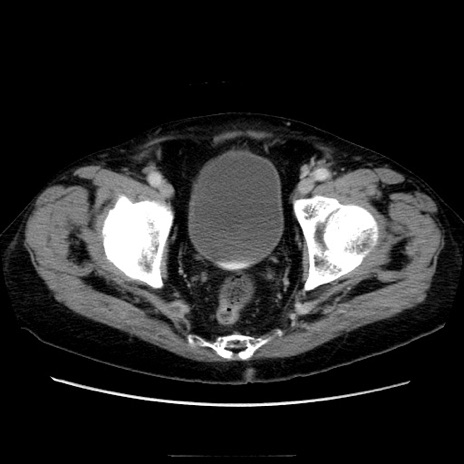

冠状断像

症例21(横断像)

【症例】70歳代男性

【主訴】腹痛

【現病歴】肝硬変・肝細胞癌にてかかりつけの方。約9時間前に食後より腹痛出現。症状が徐々に増悪し、嘔吐出現したため来院。

【既往歴】肝硬変、肝細胞癌(RFA、TACE後)

【身体所見】意識清明、表情苦悶様、BT 36℃、BP 129/78mmHg、P 88bpm、SpO2 97%(RA)、右上腹部から心窩部にかけて圧痛あり、反跳痛なし、筋性防御あり。

【データ】WBC 5800、CRP 0.16